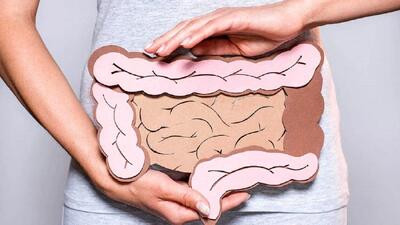

رازهای سلامت روده: راهنمای جامع برای سلامت گوارش و هضم + جدول

خط سلامت: سلامت روده یکی از عوامل اساسی و غالباً نادیده گرفتهشده در بهبود کیفیت زندگی است. میکروبیوم روده، با ایفای نقشهای حیاتی در هضم غذا، تقویت سیستم ایمنی و حتی تاثیرگذاری بر سلامت روان، به عنوان یکی از کلیدهای تندرستی بدن محسوب میشود.